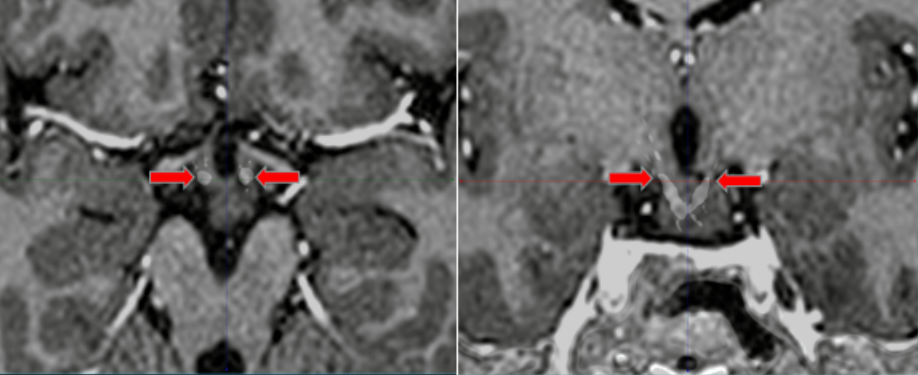

电极植入术后融合照片

电极位置良好 完全覆盖瘤蒂

下丘脑错构瘤对于瘤蒂的处理非常关键,处理好瘤蒂才能保证术后的效果。患者三维的头部核磁共振发现病变形态特殊,仅有两个很细的瘤蒂从两侧与脑组织相连,瘤蒂直径最细的地方约1mm,最粗的地方也不超过2mm;如何将直径为0.8mm的电极精准的穿过瘤蒂,成为手术的主要难点,如果有任何哪怕0.5mm的偏差就有可能使电极位置偏移而监测不到异常的放电也无法通过毁损起到彻底阻断放电传导的效果。手术计划最终设计了两根电极,分别沿两侧的瘤蒂长轴穿过,保证对瘤蒂的彻底处理。在成功“消灭”了患者颅内的错构瘤后,将电极安全取出,既保障癫痫灶毁损、又保护了手术的安全性,解决了小文多年癫痫发作的问题。